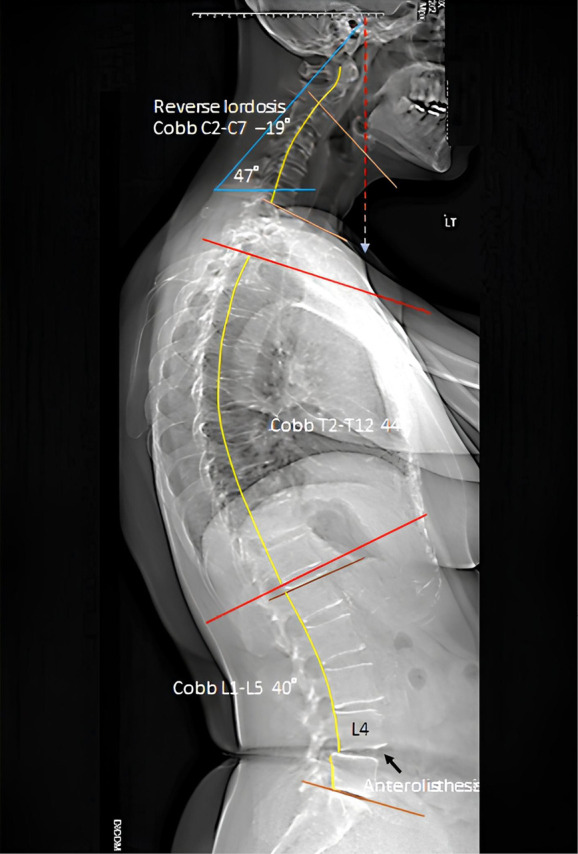

Case description: This case study involves a 60-year-old female office manager who had been suffering from neck and right shoulder pain for five years. Her family doctor diagnosed her with cervical spondylosis with cervical syndrome based on radiographic findings. She took pain medication for a year, underwent ten physiotherapy sessions and monthly massage therapy. This did not alleviate her problems, but caused her head slowly droop forward. EOS® radiography at the first chiropractic consultation showed reverse lordosis of the cervical spine, degeneration of the C4/5, C5/6, L3/4, L4/5, and L5/S1 intervertebral discs, and marginal osteophytes. A working diagnosis of age-related hyperkyphosis and cervical postural syndrome was made based on the main symptoms and clinical findings. After a 24-month multimodal chiropractic treatment program, the corrected thoracic curvature resulted in the simultaneous remission of cervical symptoms.